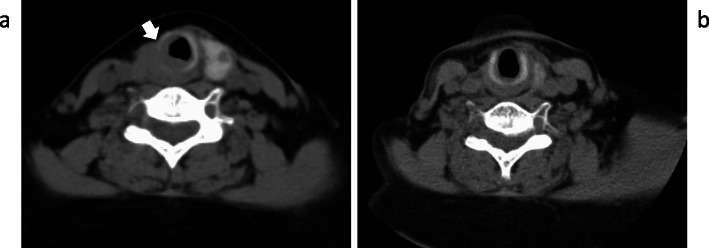

Fig. 8.

CT findings before and after radiation. a Stenosis of the trachea occurred due to recurrent tumor invasion (arrow). b The recurrent tumor could not be recognized 1 year after radiation therapy.